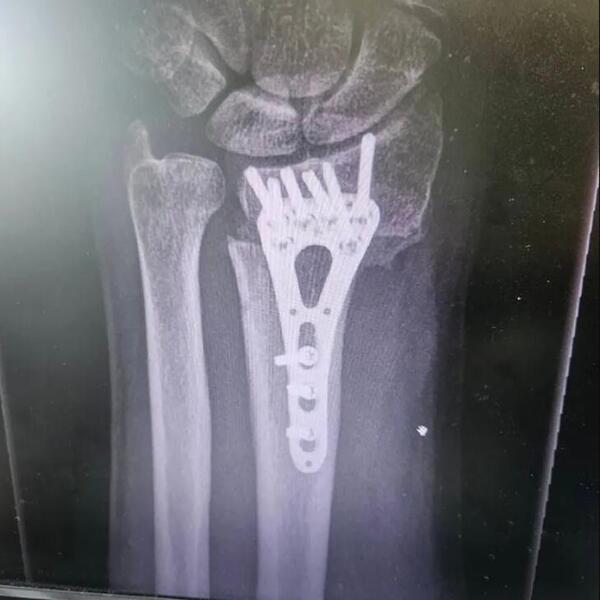

Hrvatski voditelj Aleksandar Stanković doživeo je jezivu povredu zbog koje je hitno operisan.

On se povredio pre 3 meseca, a sliku iskrivljene ruke objavio je na mrežama.

- Ovako je to izgledalo prije 3 mjeseca, a danas je sve u redu. Slomio sam ruku ( prva fotka) i operisali su me u Općoj bolnici Sisak na čelu s dr. Abel Balaško. Ruka je zacijelila i hvala im što su svoj posao odradili profesionalno i s ljubavlju!